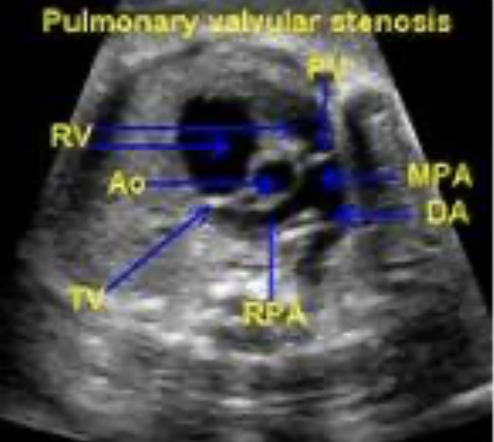

Pulmonary Stenosis

Definition?

A

narrowing/thickening/obstruction of the PV that impedes systolic flow traveling fro the RV, though the PV, into the PA. Similar to AS

• subvalvular (infundibular) PS: an obstruction of the RVOT (below the valve)

• valvular PS: an obstruction of the PV cusps

• supravalvular PS: an obstruction in the PA (above the valve)

What are the echo findings?

• thickening if the PV leaflets with systolic doming

• RV hypertrophy due to RV pressure overload = increased afterload

• flattening if the IVS due to the RV pressure overload *D shaped LV (can be visualized in PSAX)

• RA enlargement

• RV failure in the later stages of PS

• post-stenotic dilatation of the MPA due to the high velocity PS jet striking the PA wall *similar to AS